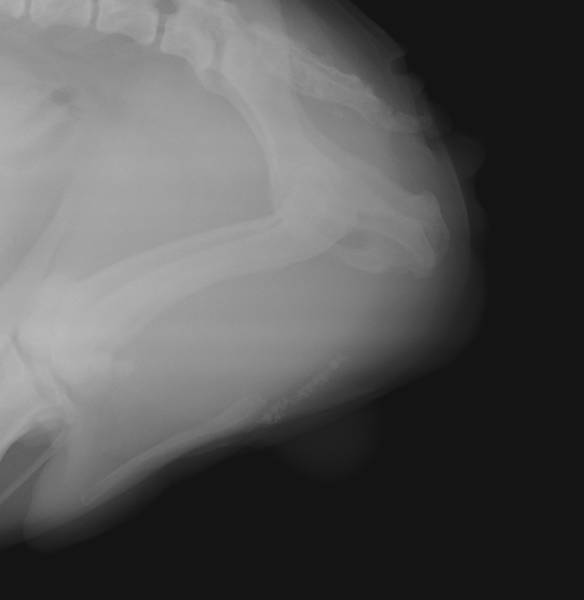

Nous pouvons alors pratiquer une uretrostomie, chirurgie qui consiste a créer un nouvel orifice en abouchant l’urètre directement a la peau dans sa zone la plus large et en amont du point d'obstruction.

Parfois des calculs volumineux sont déjà présents dans la vessie, nécessitant aussi une cystotomie, chirurgie qui consiste a aller chercher ces derniers directement sur place.